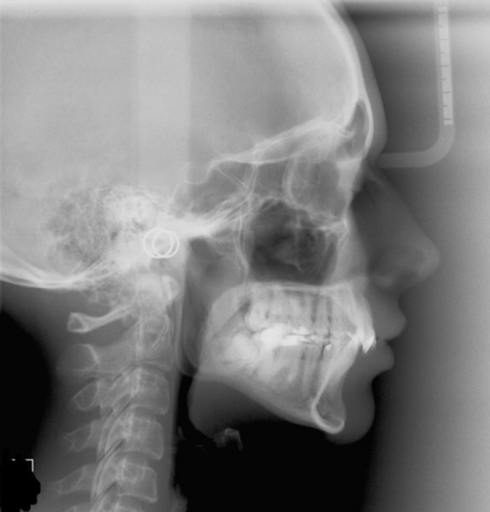

Skeletal and skull disharmony

Can orthognathic surgery help your head look more better and balanced since the bones are connected from the jaw to the skull. Or could I get any treatment from a oral surgeon for my skull irregularities?